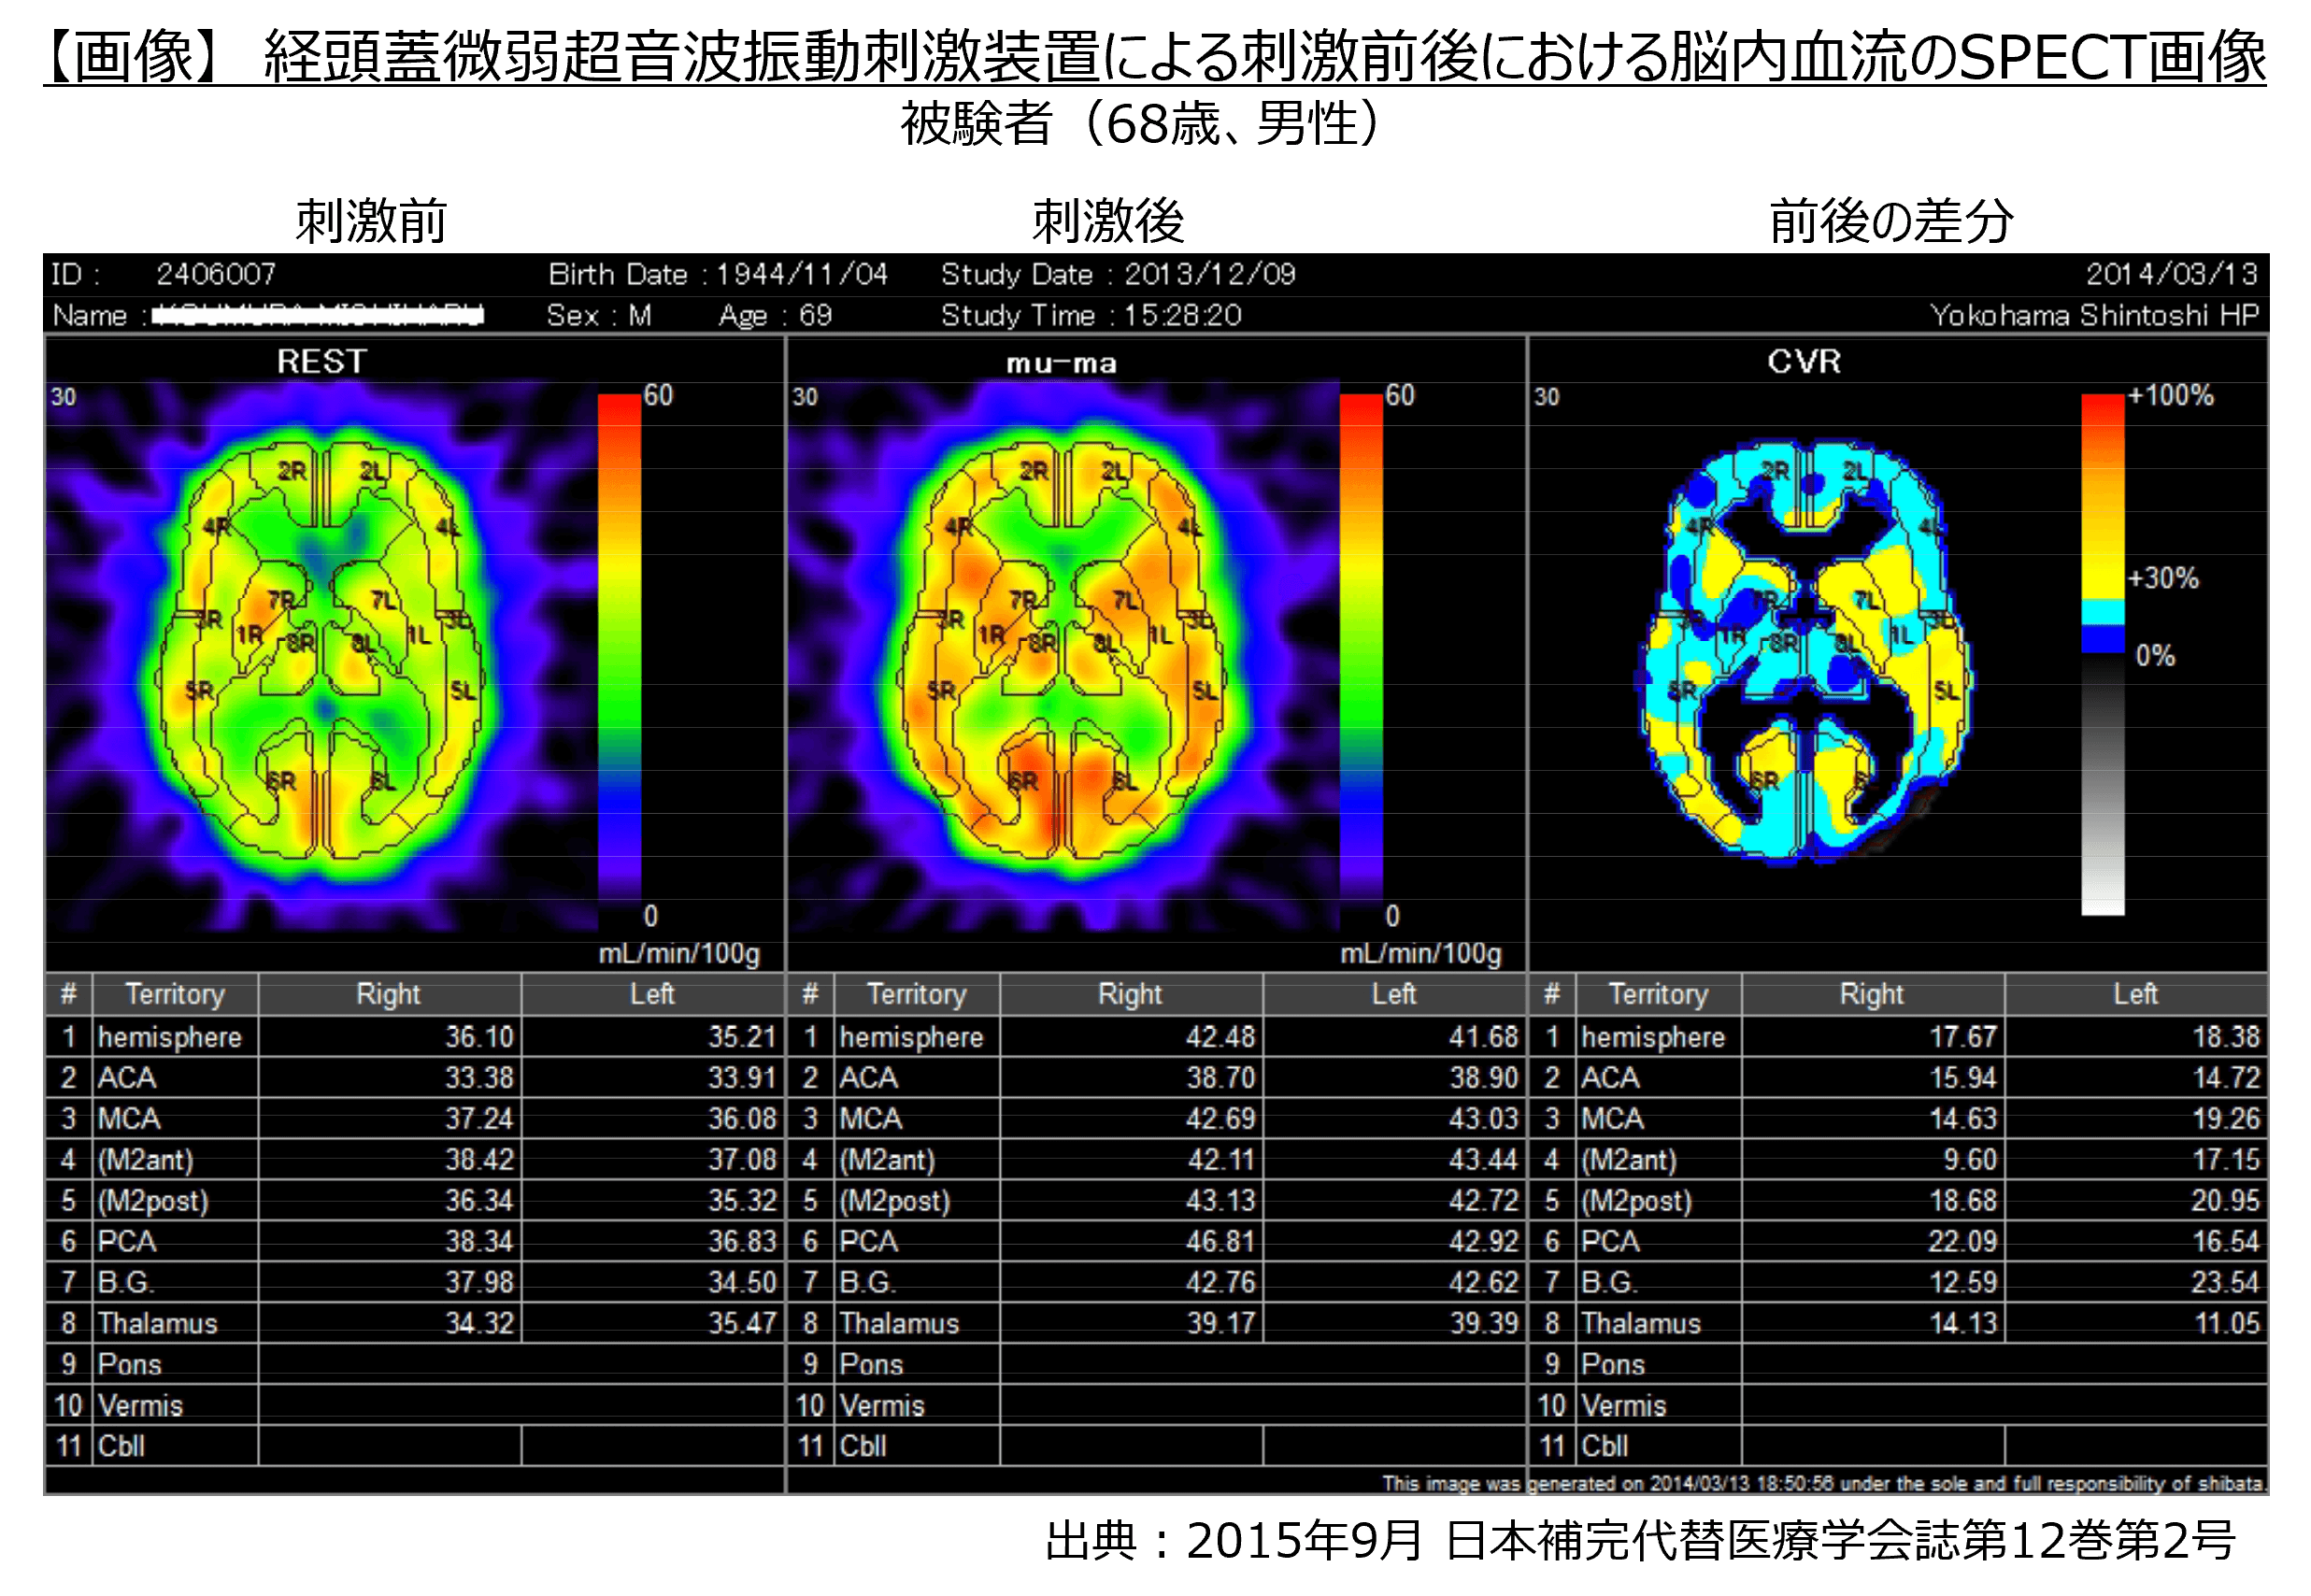

・その結果、イルカが発する30kHzの周波数帯で微弱な振動(2ミリワット/cm2以下)を初老期の健常人に20分間照射することにより脳血流が約15%増加したことが確認されました。

・故小阪憲司先生(世界で初めて脳内・異常蛋白質が原因となるレビー小体型認知症を報告、横浜市立大学名誉教授・精神科医)のご指導のもと、神奈川歯科大学附属病院 認知症・高齢者総合内科 眞鍋雄太教授とともに、中等度のDLB患者に対して特定臨床研究を実施した結果、特に運動機能障害の顕著な改善が認められました。(下記画像参照)